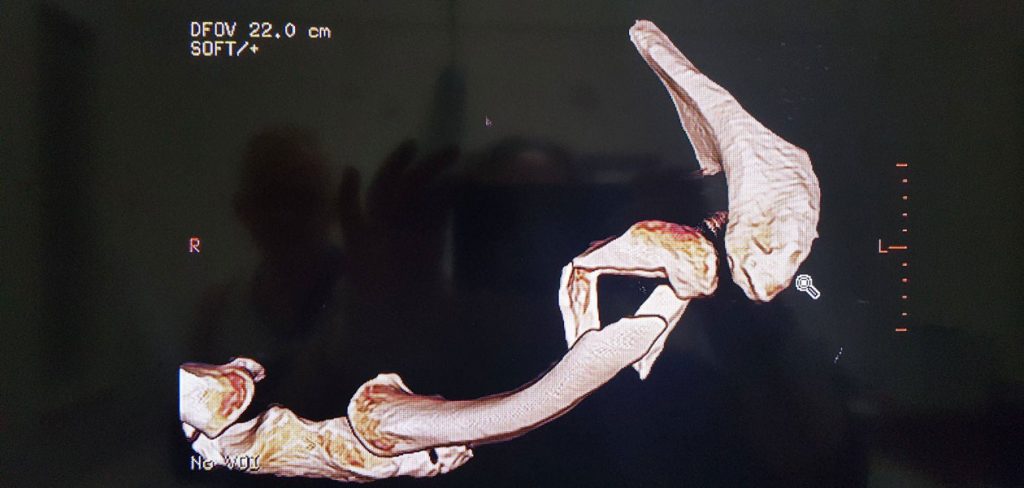

Finally out of surgery at 10pm on Wed night. To be honest it’s been a rough 24-36 hours since then, but now finally on the mend. The surgeon certainly had his work cut out for him, installing 9 screws and a titanium plate. Luckily he had all the parts as Bunnings had already closed. It’s just a shame they don’t use carbon fibre (much lighter and more aero), and had I thought about it beforehand, I would have insisted they install a Garmin mount on the plate. Thanks heaps for all your messages of support, and of course to Megs who has been my 24-hour resident nurse.

A bit shocked to see this graphic come up so soon for Ironman WA. Anyway, with recent circumstances, thought I’d do a bit of a diary for motivation come December 2. Week T-18 started a little different compared with the prior week. From feeling stronger than ever and starting to put into practise the learnings from my stomach lab testing at Monash, I then found myself recovering from surgery on maximum-dose pain killers, and hearing that a full swim and run recovery may take up to 12 weeks, instead of the 6 weeks I’d initially heard in the ER straight after the accident. So the game has changed – Busso will now be about making the start line. In the meantime, there’s 18 weekly sets of goals to hit, and hopefully with some serious effort and good healing, some of those goals will come before Week T-6. This week: rest up to let the injuries start to knit and come to accept the new reality. #IMWA #TriAlliance